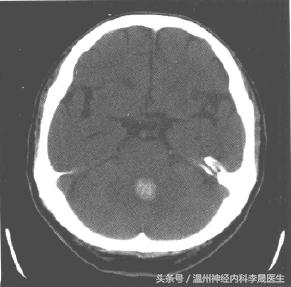

原发性脑室出血

少见,为脑室内脉络丛或室管膜下动脉破裂所致,占3%-5%. 其临床特征如下:

① 小量出血:多数。

头痛、呕吐,意识障碍或一过性意识障碍,脑膜刺激征及血性CSF,酷似蛛血,预后好,可完全恢复.。

② 大量出血:

突然头痛、频繁呕吐、迅速昏迷、四肢软瘫及去脑强直发作、针尖样瞳孔、眼球分离斜视或浮动等、病情危重,迅速死亡。